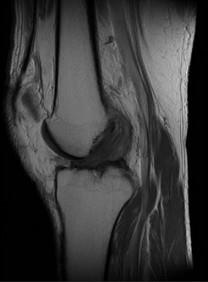

问题 男,50岁,膝关节侧方疼痛,请结合影像图像,选择最可能的诊断 ( )

选项 A、前十字韧带囊肿 B、膝关节腔积液 C、滑膜型关节结核 D、前十字韧带黏液样变性 E、化脓性关节炎

答案 D